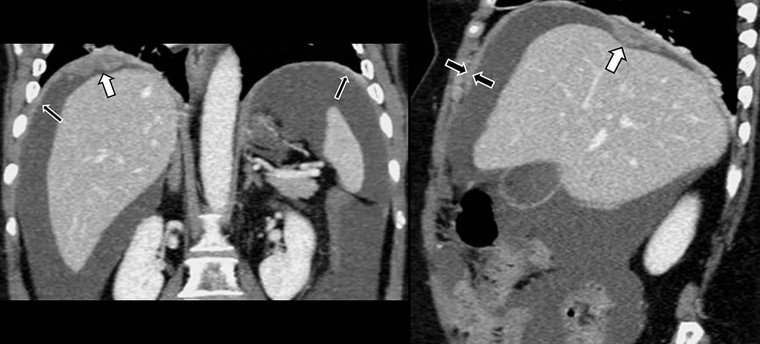

MDCT with coronal and sagittal reformations (Fig. 30-19) is considered the optimal technique for detecting the presence, location and extent of peritoneal carcinomatosis; overall diagnostic accuracy of 94%, specificity of 92% and sensitivities between 75 and 81% have been reported;22 however, sensitivity for identifying small lesions by MDCT is significantly lower. Implantation of tumour deposits along the peritoneal surfaces of the diaphragm, liver and spleen results in smooth, nodular, or plaque-like thickening and contrast enhancement of the parietal peritoneal lining. However, these features are not specific for peritoneal carcinomatosis as they may be seen with other processes that seed the peritoneum, including tuberculosis, peritoneal mesothelioma and peritoneal lymphomatosis. Contrast-enhanced T1-weighted MR images with fat saturation can improve the detection of smaller or equivocal implants or of numerous very small implants that may be manifested as a contiguous ‘line-type’ enhancement along the peritoneal surfaces (Fig. 30-20). Peritoneal tumours often enhance slowly and are best seen on images obtained 5 min after injection of gadolinium. The combination of diffuse-weighted images (DWI) and conventional MRI improves the accuracy of MRI for depicting peritoneal implants;23 therefore, DWI is suggested as an indispensable part of any MRI evaluation in patients suspected for PC.23 DW-MRI and FDG-PET/CT are promising methods for the evaluation of peritoneal carcinomatosis,23,24 but still have a limited role, especially for the identification of disease relapse after treatment. Calcification within peritoneal implants before chemotherapy suggests that the primary site is either serous papillary cystadenocarcinoma of the ovary, or, rarely, gastric carcinoma (Fig. 30-21).